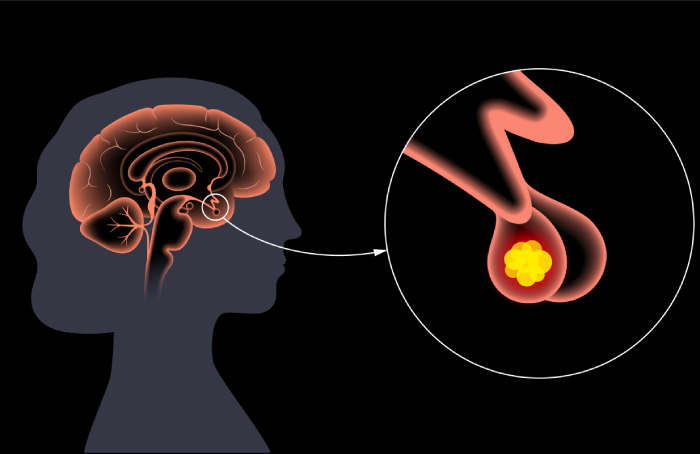

Hiperprolactinemia

Tratamiento y manejo de la hiperprolactinemia, una condición caracterizada por la elevada producción de prolactina, que puede afectar la fertilidad y la función menstrual. Nuestro enfoque incluye diagnóstico preciso y terapias adaptadas a cada paciente.

Adenomas de Hipófisis

Manejo especializado de adenomas hipofisarios, tumores benignos que pueden influir en múltiples funciones hormonales. Ofrecemos opciones desde monitoreo hasta tratamientos avanzados dependiendo de la actividad y tamaño del tumor.